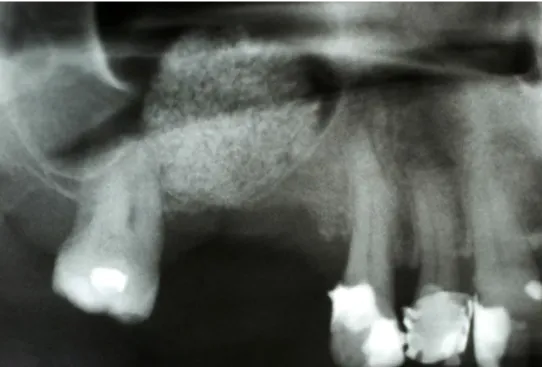

Odbudowa kostna w ODCINKACH BOCZNYCH SZCZĘK - PODNIESIENIE DNA ZATOKI SZCZĘKOWEJ (SINUS LIFT)

Technika odbudowy kostnej stosowana w celu wszczepienia implantów w zanikłe, boczne odcinki szczęk. Najistotniejszą przyczyną utraty kości wyrostka zębodołowego szczęk w odcinkach bocznych są ekstrakcje zębów. Niedostatek kości w wymiarze pionowym stanowi szczególną anatomiczną przeszkodę dla implantacji w okolicy dna zatoki szczękowej. Chcąc odbudować uzębienie i przywrócić funkcję żucia, trzeba podjąć wieloetapowe leczenie rekonstrukcyjne.

Zabiegiem, który rozwiązuje ten problem, jestpodniesienie dna zatoki szczękowej (sinus lift), czyli odbudowa kostna w okolicy zębów trzonowych. Ubytek kości uzupełniany jest materiałem kościotwórczym, który układany jest pod błoną wyścielającą zatokę szczękową, zwaną membraną Schneidera. Zmniejszając objętość zatoki szczękowej, tworzy się tym samym stabilną strukturę kostną, umożliwiającą zabieg implantacji wszczepów śródkostnych.